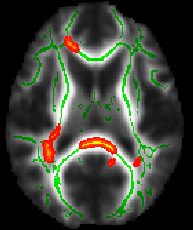

Alternatively, although showing the stats results on the TBSS skeleton is a true representation of the actual analysis carried out, some people find it easier to visualise the results if the skeletonised results are "thickened" somewhat. In order to make such a presentation easy, there is a script tbss_fill, which thickens the thresholded stats image, filling it out into the local "tracts" seen in mean_FA. For example, to apply this to the same example as above and then view in FSLeyes on top of the mean_FA image, run:

tbss_fill tbss_tfce_corrp_tstat1 0.95 mean_FA tbss_fill

fsleyes mean_FA -dr 0 0.6 mean_FA_skeleton -cm green -dr 0.2 0.7 tbss_fill -cm red-yellow